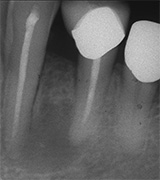

Dieser Zahn wurde schon geraume Zeit zuvor von einer Kollegin im Notdienst eröffnet und anschlies­send mit einer aufwendigen Amal­gamrestauration ästhetisch an­sprechend wieder verschlossen. (Bild 1) Uns blieb noch WK/WF, was bei massiver Überstopfung der hin­teren Wurzel auch gelang (Bild 2).

"Überstopfen ist immer noch besser als Unterstopfen" laut Koçkapan. OK, hier wurde des Guten aber ganz eindeutig zuviel getan.

Also direkt neben dem Zahn das Zahnfleisch ein wenig angehoben und zur Seite gedrängt und dann mit einem scharfen Löffel den Überschuss vollständig entfernt.

Schon 8 Monate später ist eine deutliche Verbesserung der Gesamt­situation unverkennbar (Bild 3). Verlorengegangene Knochensubstanz wurde in Teilen schon wieder aufge­baut, doch ist noch gar nichts entschieden. Schaun mer also ma'.

Abrechnungstechnisch hat der Mut zur WR an 38 gefehlt, deshalb nur EXZ1.